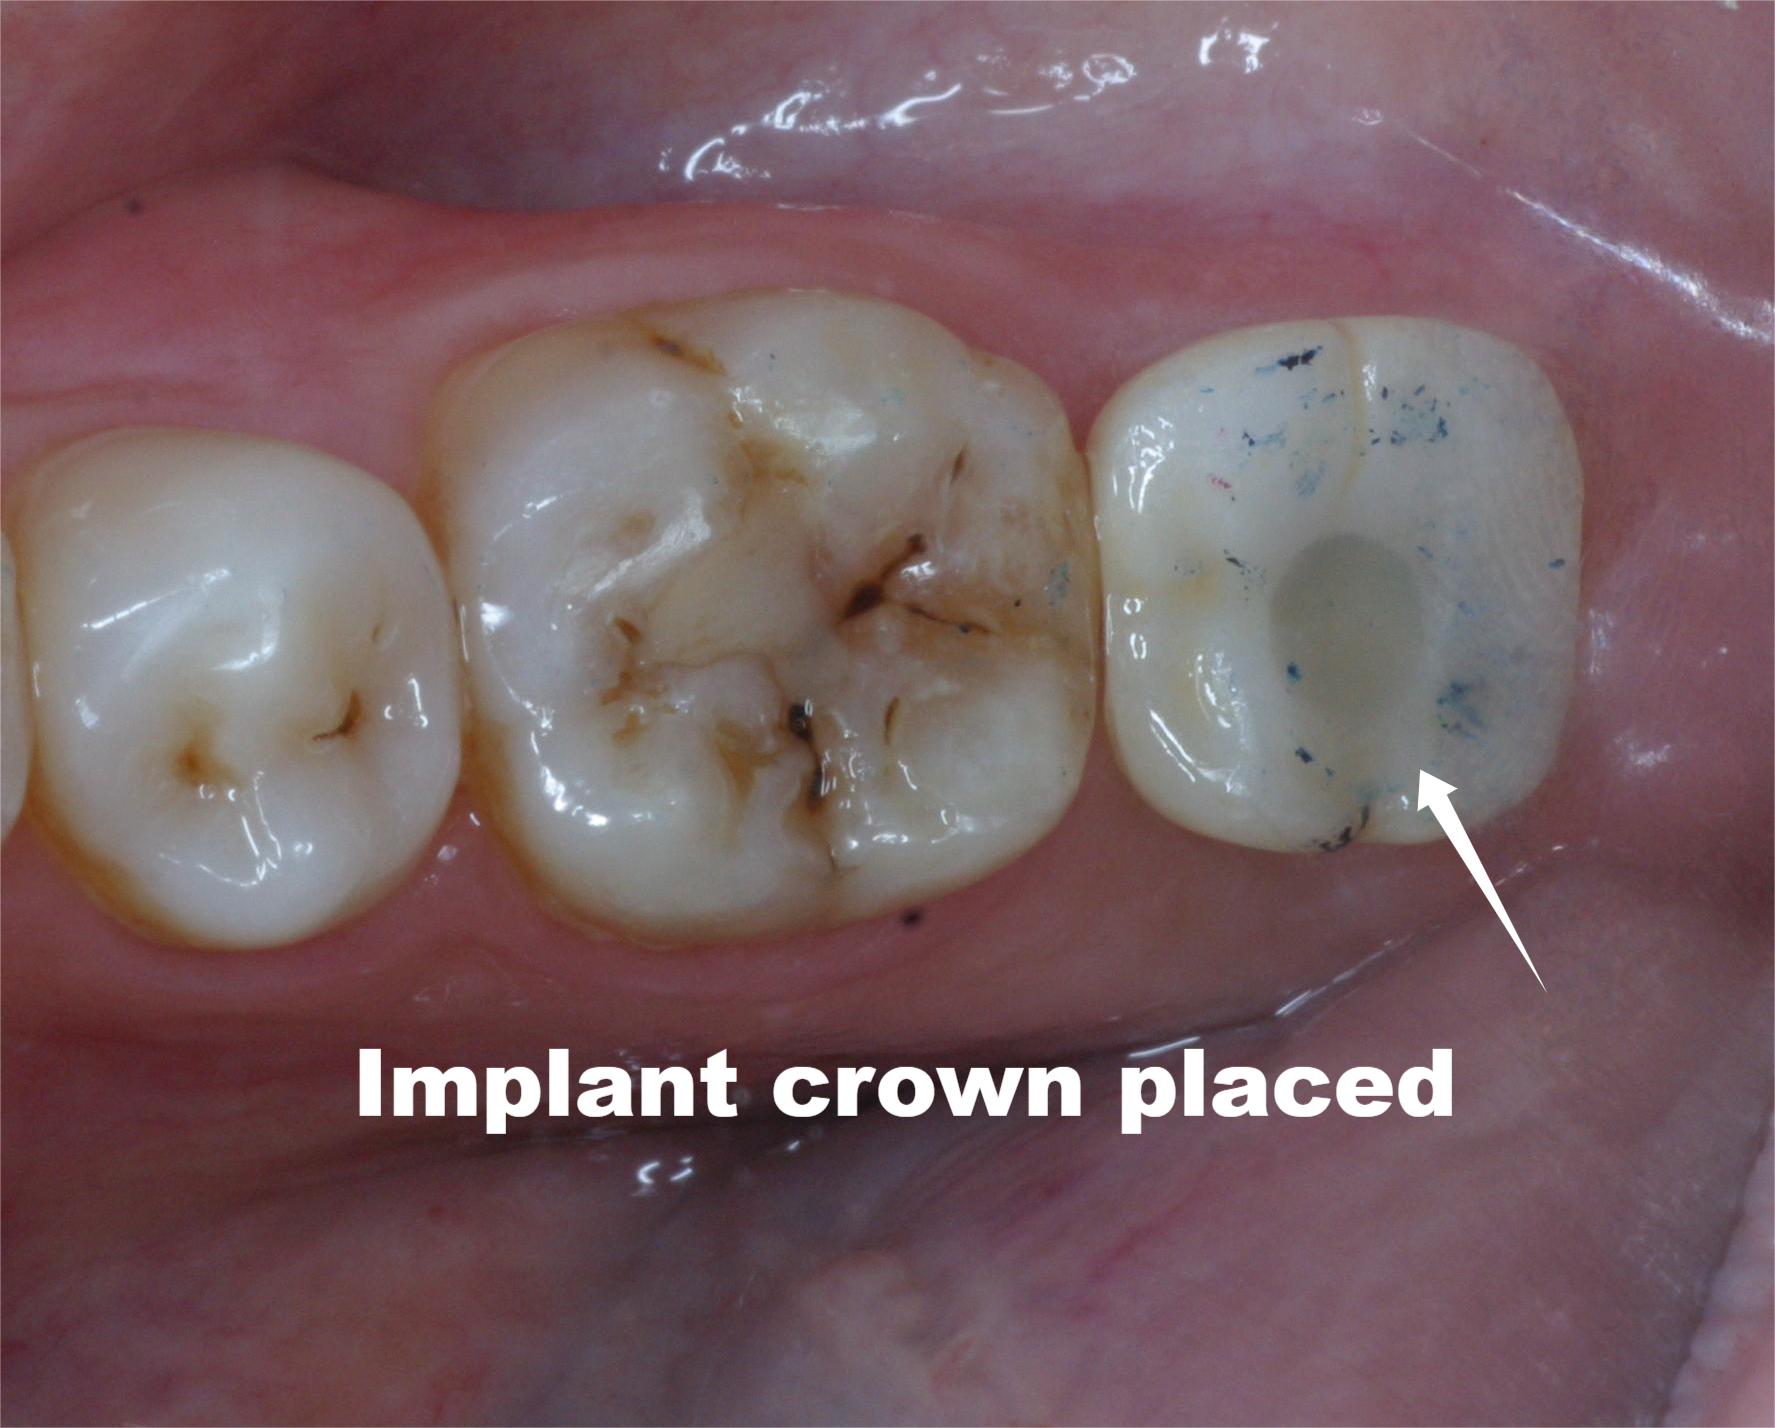

Once healed, we attach the custom crown, your new tooth that looks, feels, and functions naturally.

Actual patient results. Individual outcomes may vary.